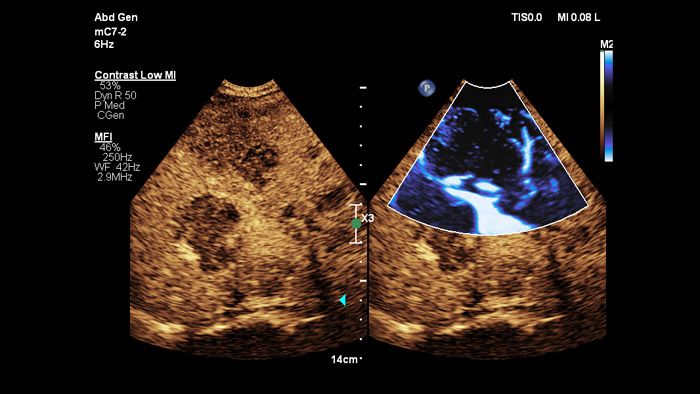

Les agents de contraste échographiques peuvent transformer le rôle de l'échographie dans l'évaluation du foie en permettant d'étudier les schémas de rehaussement des lésions hépatiques suspectes en temps réel pour un diagnostic plus rapide et plus sûr.